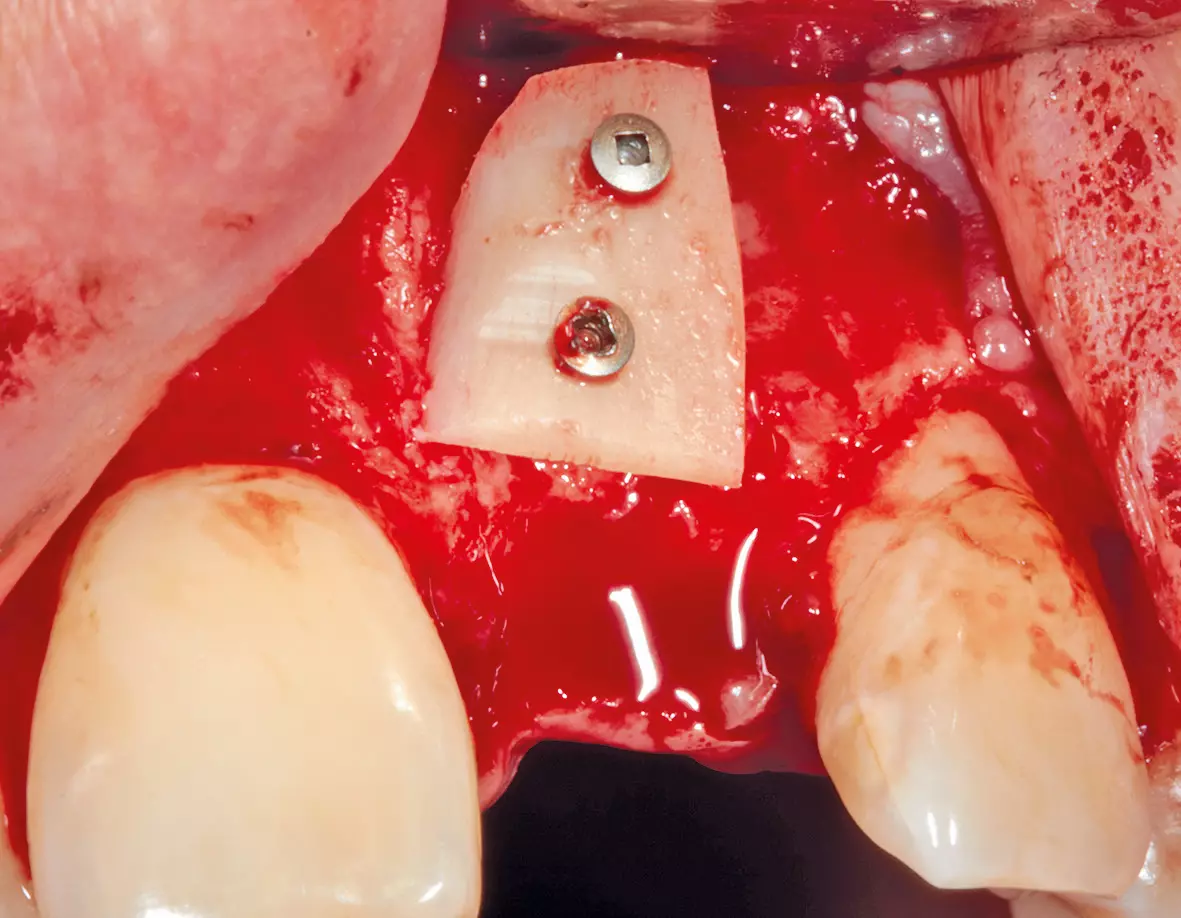

Augmentation

Nach der Heilungsphase war für einen Aufbau der vestibulären Lamelle ein Knochentransplantat aus dem Kieferwinkel erforderlich. Dies sorgte für eine gute und gleichmäßige Ausformung des Vestibulums und es bestand die Möglichkeit, das Implantat an die gleiche Stelle wie die Zahnwurzel zu setzen (Abb. 5 und 6).